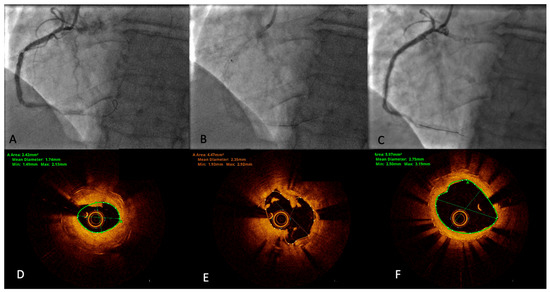

First-in-Center Experience with a Novel Intravascular Lithotripsy System: The Shunmei ShockFast™ Intravascular Lithotripsy System Device for the Treatment of Severe Calcified Coronary De Novo Lesions

Background: Intravascular lithotripsy (IVL) has emerged as a safe and effective modality for treating severely calcified coronary lesions. While the Shockwave™ system is well-established, clinical data on newer IVL platforms such as the Shunmei ShockFast™ system remain limited. Objectives: To evaluate the safety, [...] Read more.

Background: Intravascular lithotripsy (IVL) has emerged as a safe and effective modality for treating severely calcified coronary lesions. While the Shockwave™ system is well-established, clinical data on newer IVL platforms such as the Shunmei ShockFast™ system remain limited. Objectives: To evaluate the safety, feasibility, and procedural outcomes of the ShockFast IVL device in patients with heavily calcified de novo coronary artery disease. Methods: We conducted a prospective, single-center case series of 16 patients undergoing percutaneous coronary intervention (PCI) with the ShockFast IVL system between June and December 2025. Inclusion required angiographic or optical coherence tomography (OCT) evidence of severe coronary calcification. The primary efficacy endpoint was acute procedural success and absence of in-hospital MACE. Secondary endpoints included, among others, device deliverability, presence of calcium fracture and post-stent expansion metrics. Results: All patients underwent successful lithotripsy delivery with the ShockFast IVL system. Acute procedural success was 100%, with no intraprocedural complications, abrupt closure, or in-hospital MACE. OCT was performed in 50% of cases and demonstrated calcium fractures in all imaged lesions, with ≥2 fractures in 63% of cases. Median stent expansion was 90% [IQR 9], with no major malapposition or edge dissections. Quantitative coronary analysis showed a median acute lumen gain of 1.86 mm [0.62]. Conclusions: The ShockFast IVL system showed excellent safety and procedural performance in this first-in-center experience. Outcomes were encouraging and consistent with those reported in early-stage studies of other IVL platforms. These findings support the clinical feasibility of ShockFast as a novel tool for calcium modification in complex PCI. Full article